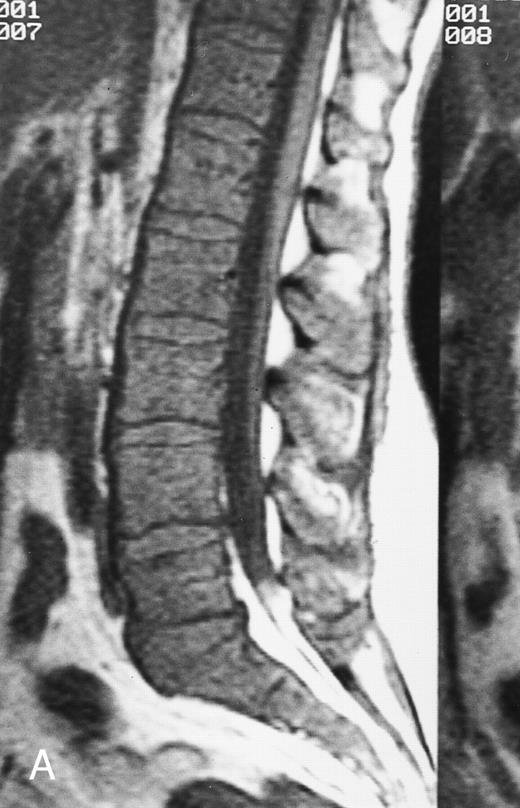

T1-weighted (500/11, TR/TE) sagittal MR images of the lumbosacral spine in a 45-year-old woman before (A) and 40 days after (B) bone marrow transplantation for multiple myeloma. There is a diffuse MR pattern of marrow involvement in (A) (bone marrow plasma cells, 50%; monoclonal protein, 6.0 g/dL). On the posttreatment image, there is definite reinstitution of fatty marrow in the spine and, in particular, around the basivertebral veins, in keeping with partial response to treatment (bone marrow plasma cells, 0.5%; monoclonal protein, 1.6 g/dL).